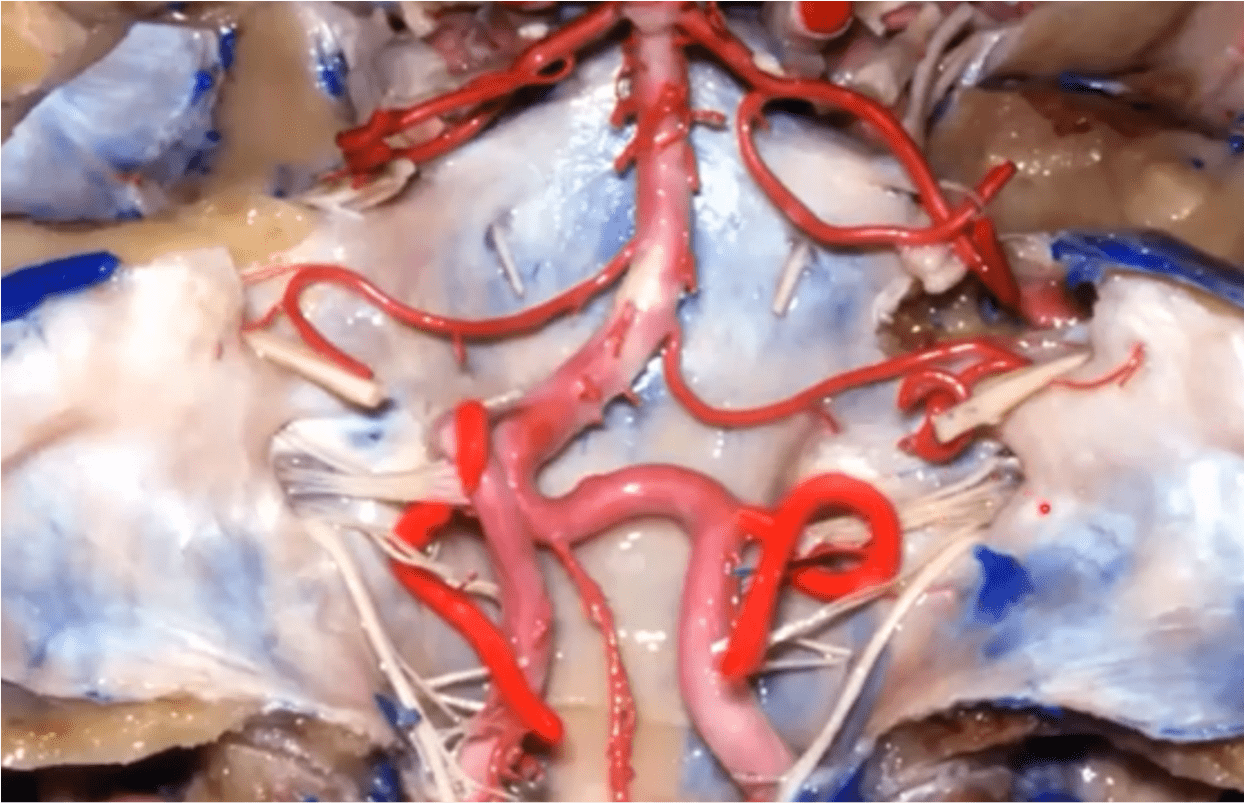

Name the highlighted artery

Posterior Inferior Cerebellar Artery (PICA)